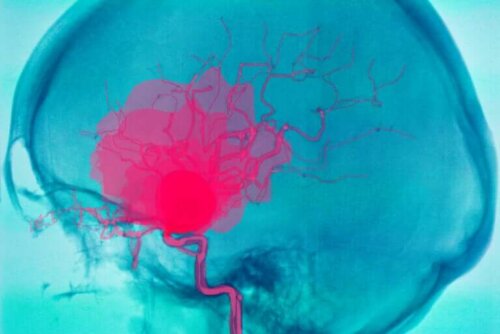

L’hémorragie cérébrale est une situation grave qui peut mettre en danger la vie de la personne qui en souffrent. Elle consiste en un saignement à l’intérieur du cerveau, qui fait que le sang coule et ne va pas correctement vers toutes les parties de l’organe.

Une hémorragie cérébrale, comme nous l’avons signalé dans l’introduction, est un saignement qui se produit à l’intérieur du cerveau. Elle provoque généralement des défauts neurologiques qui surgissent brusquement et même un coma.

Ceci est dû au manque d’irrigation sanguine vers le reste des parties du cerveau car le sang ne continue pas son trajet dans les vaisseaux sanguins. Il est important de faire la différence entre hémorragie cérébrale et hémorragie intracrânienne.